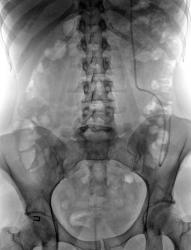

Так, это случай - загадка?

И элементарного анамнеза нет? Я чисто интуитивно догадываюсь, что "это какой-то" стент.

А изменения в поясничном отделе позвоночника Вас не смущают? Да и "перекошенный" таз чем-то надо объяснить.

Валентин Львович, пациентка ко мне напрвлена была с приемного отделения и чистого листа, однако мое предположение о так называемом "стенте" подтвердилось, другое дело если это явилось причиной почечной колики узнаю только в четверг. А пока у кого какие преположения о "стенте"?

Да, Вы правы это вентрикуло-перитониальный шунт, уже в приемном отделении я убедился окончательно. Была какая то травма связанная с ДТП, как следствие ЧМТ, в дальнейшем развитие гидроцефалии-ВПШ, передняя брюшная стенка вся в после операционных рубцах. По поводу же травматических изменений таза и поясничного отдела позвоночника, этого точно ни могу сказать. Чуть позже продемонтрирую экскреторную урографию, а пока сказать что это не является причиной почечной колики на 100% нельзя.